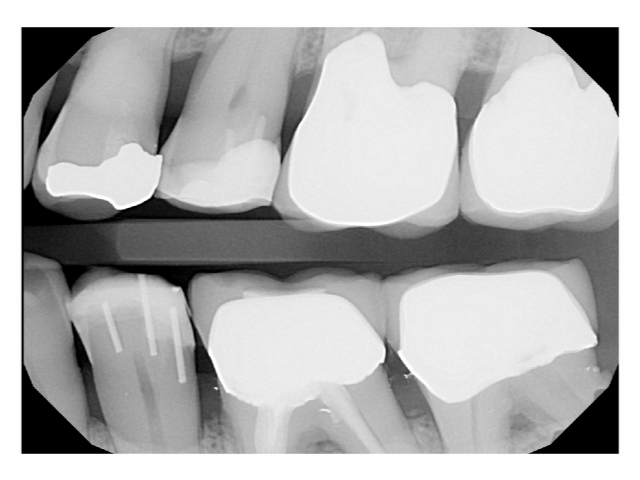

6

Broken tooth with DentXpinTM repair.